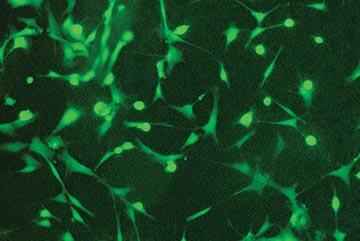

SwRI is using the bioreactors to propagate mesenchymal stem cells, which are “multipotent” with the capacity to self-renew by dividing and developing into multiple specialized cell types associated with specific tissues or organs. Most adult stem cells are multipotent stem cells.

AFTER SEEDING

DAY 2

DAY 7

These images show the propagation of stem cells in the bioreactor in a week’s time. Live cells are shown in green fluorescence.